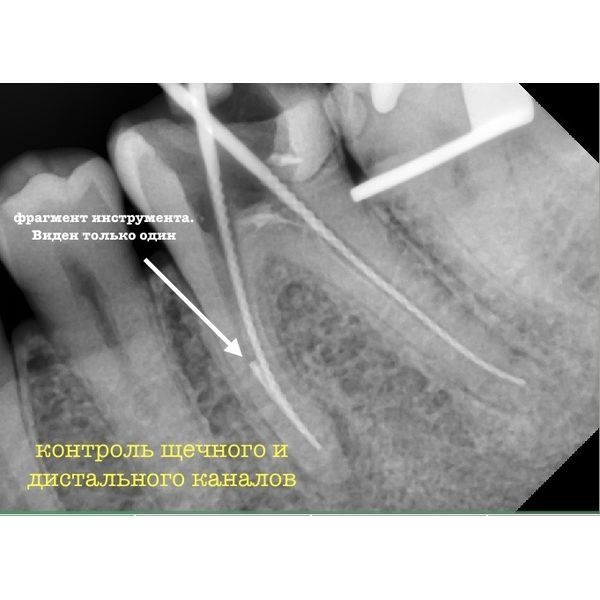

При осмотре под микроскопом можно было увидеть 2 фрагмента инструментов.

Мужчина принёс с собой два полных снимка КЛКТ, сделанных до и после вмешательства, что позволило рассмотреть анатомию корневых каналов, оценить причину фрагментации инструмента и определить точное расположение обломков.

- фрагмент инструмента в нижней трети язычного корня зуба;

Лечение проходило в 2 этапа. На первом приёме удалось извлечь один фрагмент, после чего 3 корневых канала обработали и заполнили (обтурировали) кальцийсодержащим препаратом.